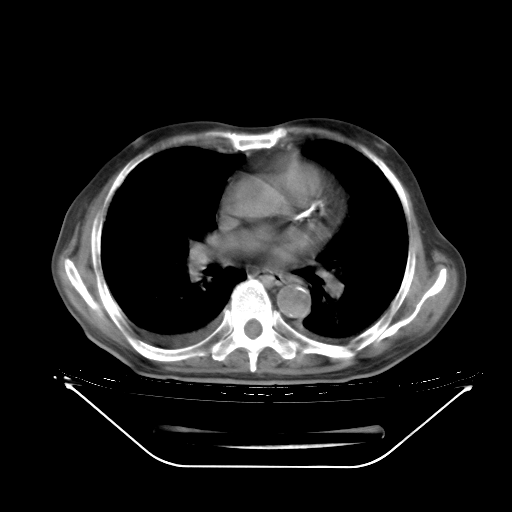

今天复查肺部CT,发现双肺广泛磨玻璃样改变。所以我把3月19日和5月9日相隔50天的肺部CT上传。请大家会诊。

5月9日肺部CT(在4月27日齐鲁医院肺部CT描述部分肺组织磨玻璃样改变,12天后肺组织广泛磨玻璃样改变)

大致读了系列胸部CT:纵隔窗无明显异常,肺窗:从4、27至今:主要是双肺中下野外带可见毛玻璃样改变,目前处于急性肺泡炎阶段,至于原因考虑1、结替组织或胶原血管性疾病所致?2、恶性疾病如恶组在肺部所致的表现或细支气管肺泡癌?3、药物或其它原因如肺蛋白沉着症所致肺泡炎目前不太可能?总之,明天就去请我院的呼吸科、感染科、血液科和临免专家会诊哈。